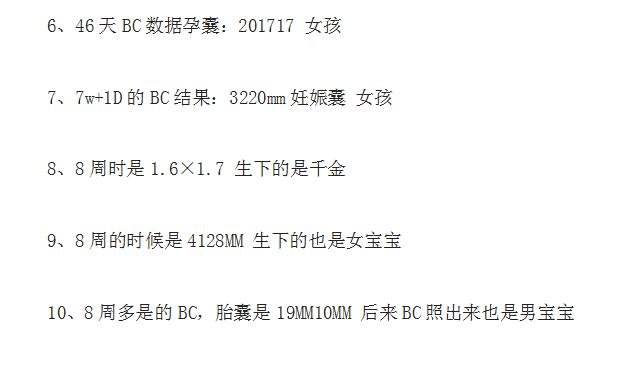

是不是准妈妈们从怀孕初期就开始期待孕子里的孩子是男是女了?因为国家

并不提倡鉴定胎儿性别,所以宝妈们对肚子里的宝宝究竟是男是女有着很大

的好奇心。在这里小编就教大家一个利用B超单上的数据来看男女的方法,

来一解准妈妈们的好奇心。